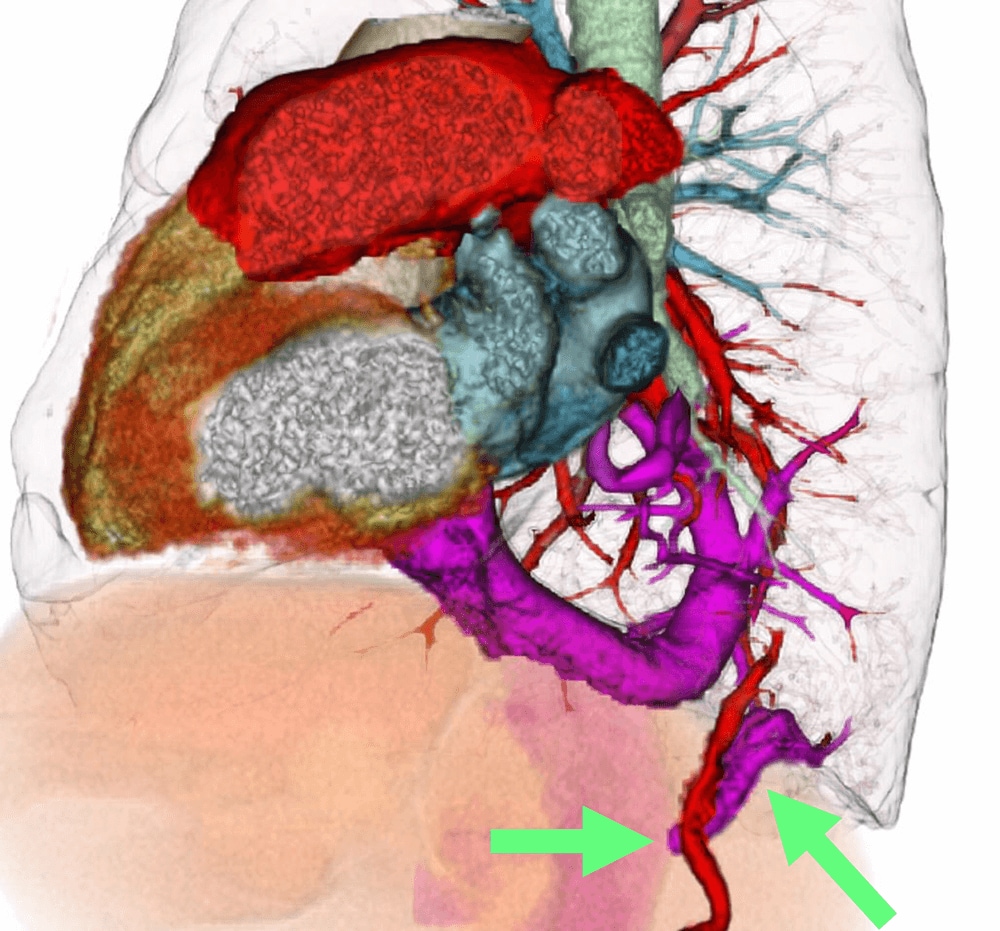

図4.3次元再構成VR像

図1-3で示した肺静脈のさらに下方の右肺底部背側に還流異常を生じた右肺静脈が、肝部下大静脈に流入している(矢印)。